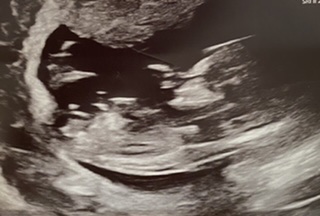

13+1 nub guess?

Hi all, I’m back after 8 years and swearing I didn’t want any more kids! This scan was taken at 13+1 my partner is pretty certain of what he saw on the screen but just wanted some guesses for fun. I’ve already had a few and all swaying the same way. TIA x

I am suspecting your partner saw that sticky outy thing and assumes it is a penis, but see how straight it is?? My guess is girl. Now, it is still a bit early, and that can and in some cases DOES rise and then babies that looked like girls will be revealed to actually be boys, but as it sits now that looks like a girl to me. :heart: huge congrats!

This is now a confirmed boy nub :BabyBoy::bigsmile:

I do want to point out that for anyone looking at this particular shot and thinking "this is just what my nub looked like, and it's a confirmed boy, so if I see this nub I must be having a boy" this is really not in any way the "classic" boy shot we would be looking for!